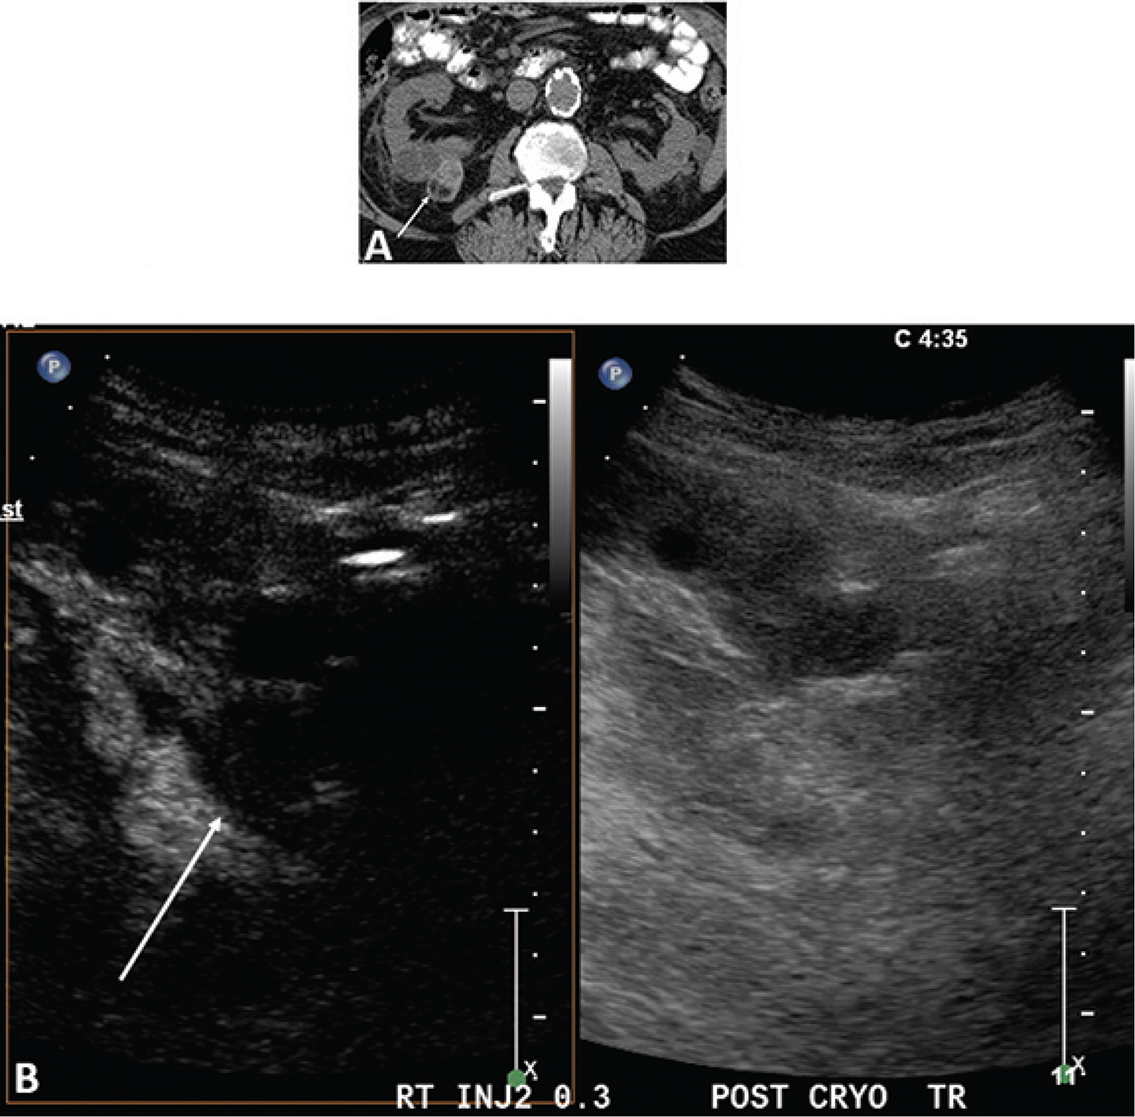

Figure 1 demonstrates the steps in performing a CEUS RFA. Figure 1A is the unenhanced B-mode US before the procedure. In this case, the mass is easily identified. If the mass is not visualized well, a CEUS can be performed to confirm the size and location of the mass. Figure 1B shows the position of the RFA needle in the mass. Figure 1C is the image after the injection of the ultrasound contrast confirming the position of the needle in the mass. Figure 1D shows that there is no flow remaining in the renal mass, confirming complete ablation of the lesion.

Figure 1. Images demonstrating RFA of an RCC. (A) B-mode image of the RCC (calipers) pre-procedure, (B) B-mode image demonstrating positioning of the RFA needle (arrow) in the RCC, (C) image after injection of ultrasound contrast confirming the needle (arrow on low MI B-mode image on right) within the tumor, and (D) CEUS post-procedure demonstrating complete ablation of the RCC (arrow, right).

Figure 2 demonstrates that after the first ablation, a second dose of ultrasound contrast can be performed to evaluate for residual tumor. The CEUS contrast lasts for about 5 min. During the RFA, gas bubbles are generated and appear as CEUS contrast when imaging. Waiting for about 5 min after the completion of the ablation will eliminate this problem. If bubbles still remain in real-time CEUS imaging, the bubbles generated from the procedure will not move whereas the UCA bubbles in residual tumor will be visualized as moving. In this case, a large area of residual tumor (arrows) remains. The CEUS image can be used to reposition the RFA needle into the residual tumor.

Figure 2. Multiple doses of ultrasound contrast can be administered during the RFA procedure. The contrast agents last for about 5 min so that residual enhancement is not present on additional doses. In this case, a CEUS study was performed after the first ablation. Note that there is residual tumor (arrows). The RFA needle can then be repositioned into the residual tumor for additional ablation. This confirms that the tumor is completely ablated at the first setting. The similar process cannot be performed in CT because only one dose of CT contrast can be administered.